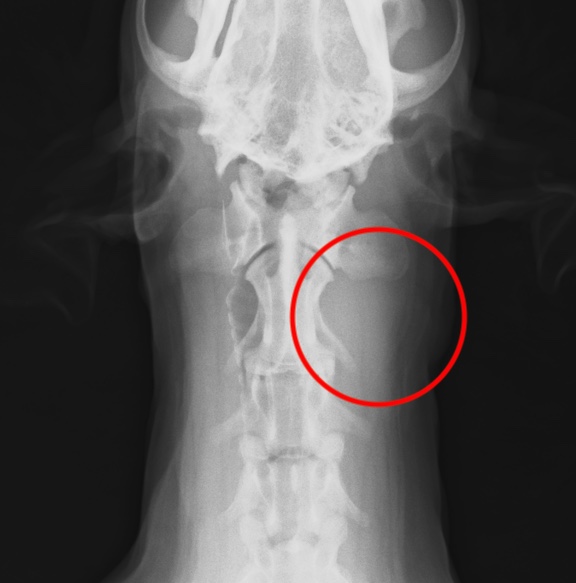

・レントゲン検査:リンパ節転移、遠隔転移(肺など)の評価

扁桃の扁平上皮癌がリンパ節転移したレントゲン画像(赤丸)